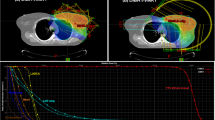

Table 2 compares plan parameters of opposed tangential beam IMRT with conventional 3D-CRT for the adjuvant radiotherapy of the chest wall in 20 unselected consecutive breast cancer patients after mastectomy. Figure 1 demonstrates typical dose distributions of an IMRT and 3D-CRT plan of the same patient.